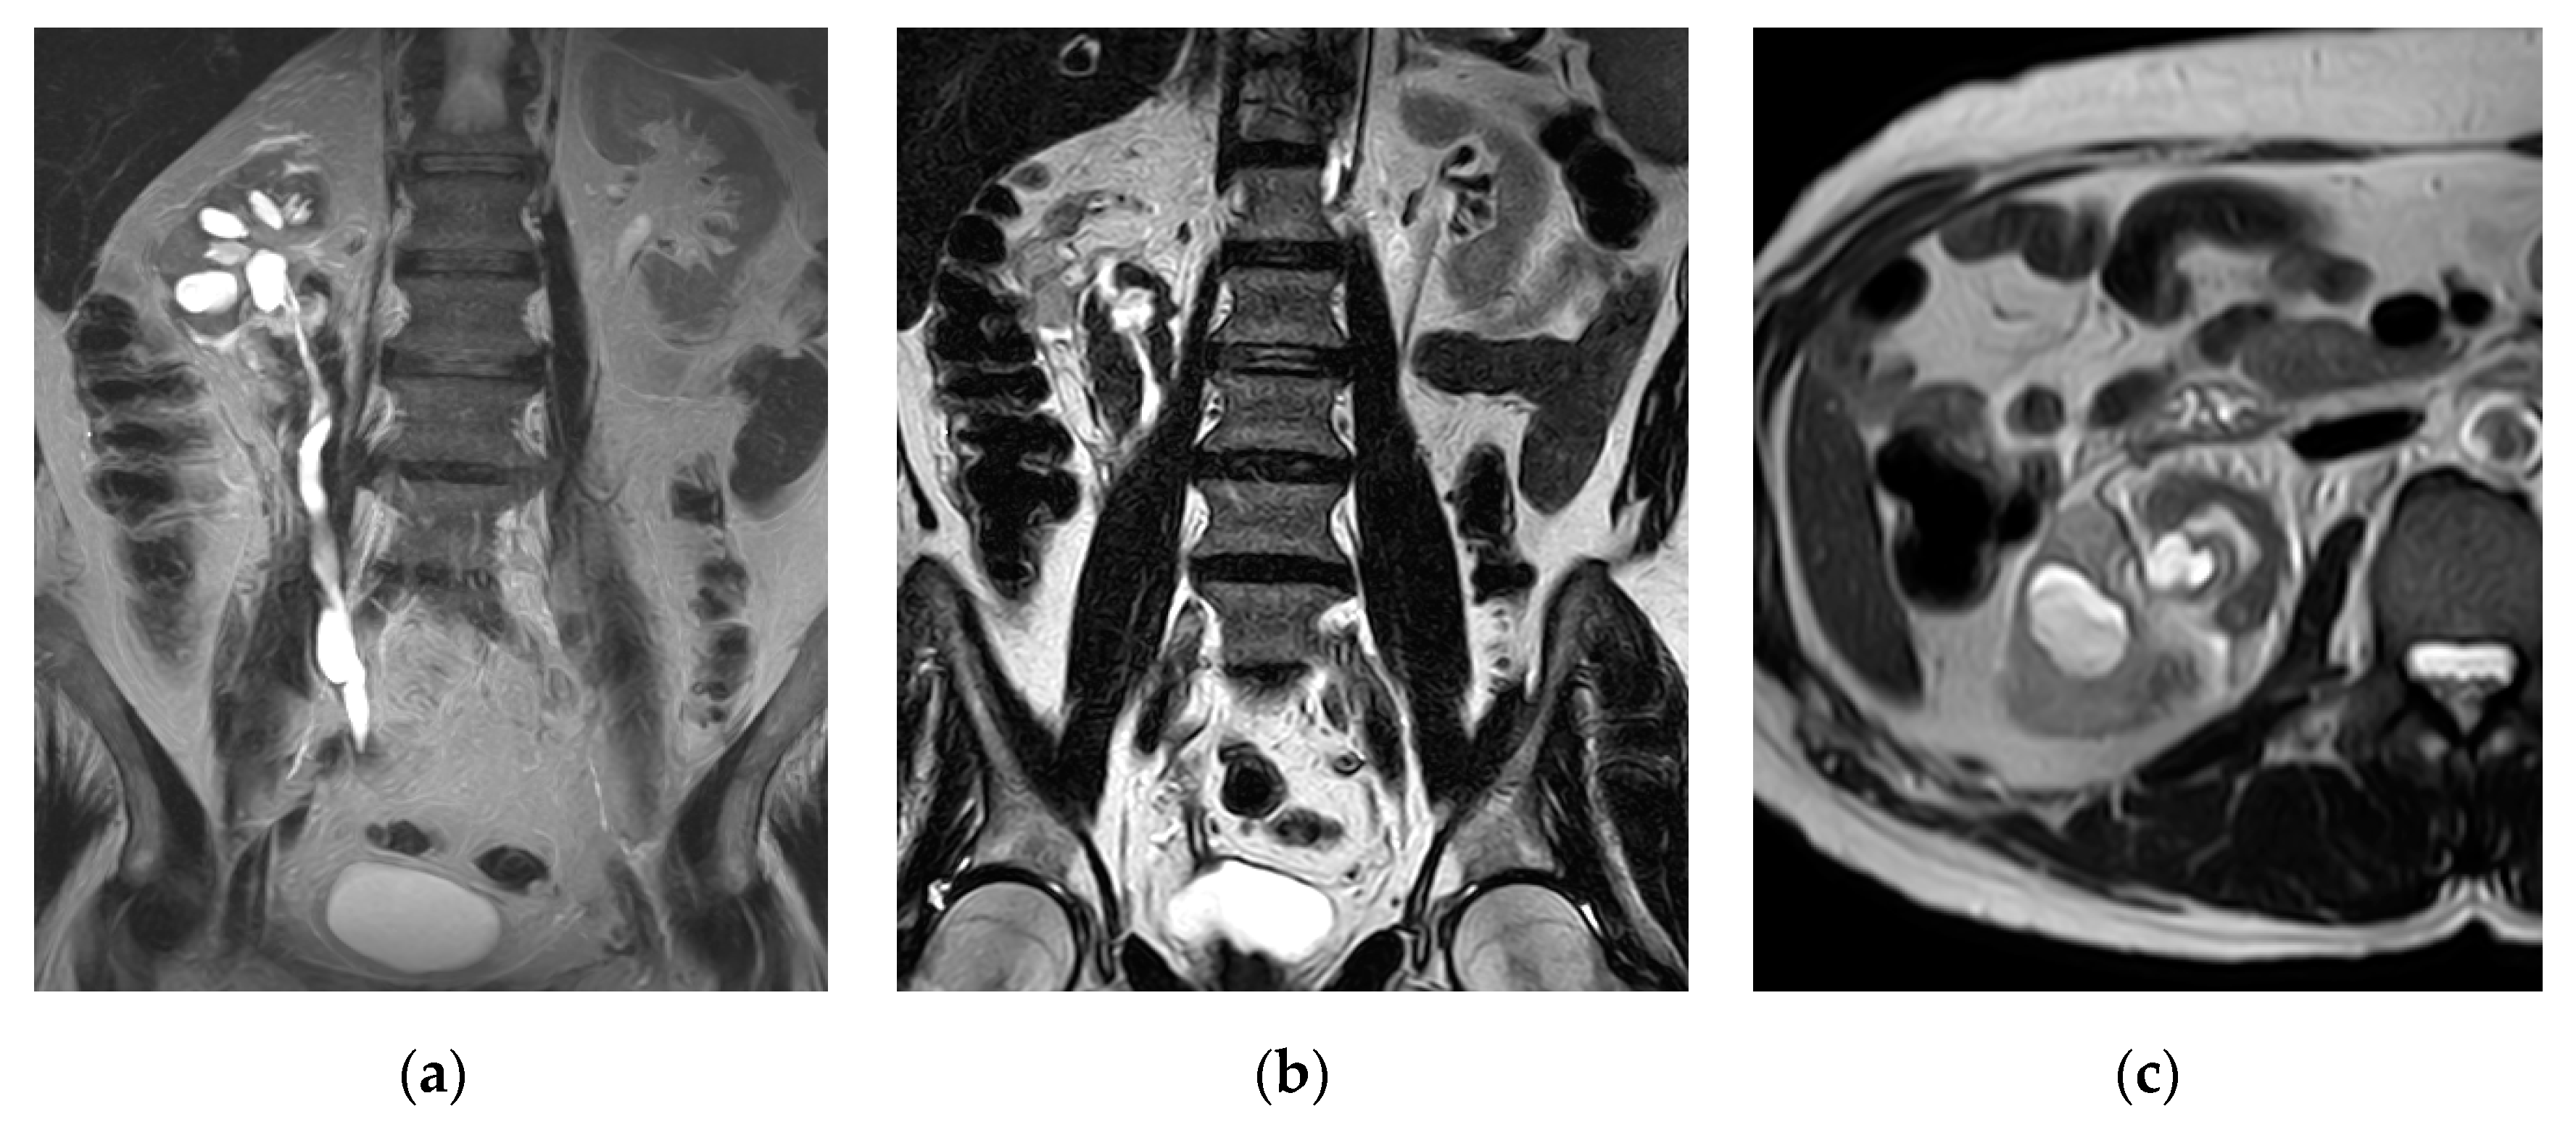

2.7. Urinary Tuberculosis

| Urinary tuberculosis | Calyx stem stenosis with proximal ball-shaped hydrocalyx, cavity communicating with a deformed calyx, putty kidney, ureteric strictures and shortening with beaded appearance, thick-walled contracted bladder. |